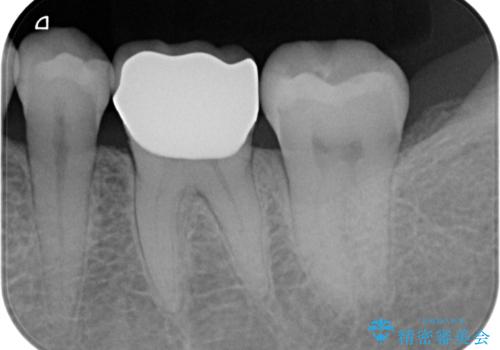

銀歯の除去・虫歯の除去を行ったのち、適合の良い精密なジルコニアセラミッククラウンを製作します。

治療後、銀歯と虫歯のない清潔な口腔内環境を達成することができました。